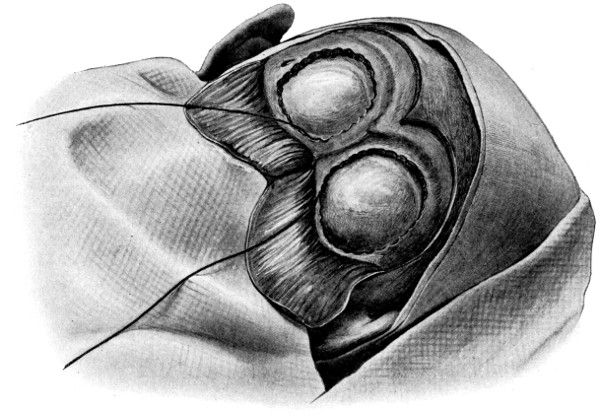

| 73 A, B, C and D. The exposure of a cerebellar tumour by craniectomy | 239-41 |

Fig. 19. Third Stage in the Formation of an Osteoplastic Flap. The dural flap turned down and the brain exposed. Note the relation of the scalp, bone, and dural incisions to one another.